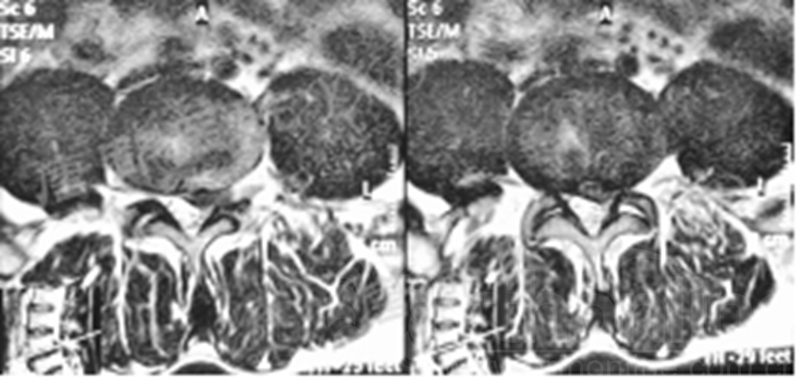

专科情况:轮椅推入病房;强迫体位;双侧直腿抬高试验、加强试验阴性;左小腿后、外侧及足背、足底皮肤感觉减退;余未见明显异常。VAS评分:左下肢7。

既往8年前因“腰4、5椎弓峡部裂并腰4椎体滑脱症”于外院行腰4~骶1椎板减压椎间植骨融合内固定术,后因椎弓根螺钉断裂于5年前行内固定取出术。

影像学检查:

诊断:腰椎椎间融合术后融合器后移

手术方案:显微镜辅助MI-TLIF腰椎翻修术

术中视频:http://api.orthonline.com.cn/attach/Case3.mp4(术中发现因前次手术全椎板及关节突切除,TLIF的第一步,即关节突关节的定位落脚点难以找到。显微镜下通过Kambin三角解剖位置,进行从外至内的解剖,寻找cage尾端;此外,因大量瘢痕渗血,难以进行充分止血;但在显微镜的照明和放大视野下,操作均可在不伤及神经的前提下进行。由于终板骨质吸收,椎间隙塌陷,导致术野内可同时看到出行根和走行根。而在显微镜下,能够通过调整景深和视线角度,精准充分处理椎间隙骨性终板。无手术并发症)